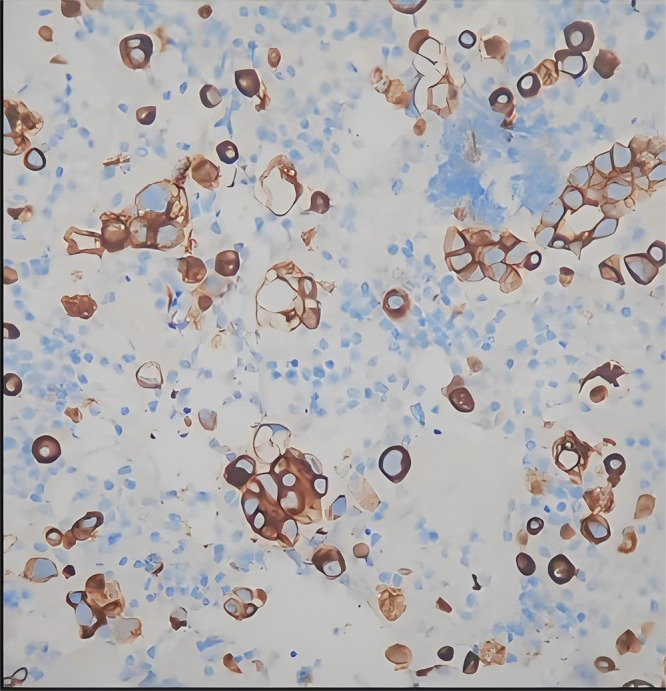

本病例报告报告了一名67岁男性,诊断为IV期肺腺癌,伴有罕见的EGFR外显子18/20突变(Gly719Cys/Ser768Ile)和并发的TP53突变,并伴有肾病综合征。针对NSCLC中罕见EGFR突变的批准EGFR- tkis的缺乏,加上肾病综合征引起的肾损害、低白蛋白血症和常规治疗难治的大量胸腔积液,促使了个性化多模式方法的发展。实施白蛋白结合紫杉醇、胸内灌注恩度(重组人内皮抑素)和中药的多模式治疗方案,实现了有效的疾病控制。值得注意的是,该治疗导致肿瘤明显缩小(RECIST 1.1的缩小率为48.1%),恶性胸腔积液完全消除,肾病综合征参数明显改善。靶向化疗、抗血管生成治疗和基于中药的症状调节的协同作用,突出了综合治疗具有复杂分子特征和多系统并发症的晚期恶性肿瘤的潜力。

This case report presents a 67-year-old male diagnosed with stage IV lung adenocarcinoma harboring rare EGFR exon 18/20 mutations (Gly719Cys/Ser768Ile) and a concurrent TP53 mutation, complicated by nephrotic syndrome. The scarcity of approved EGFR-TKIs targeting rare EGFR mutations in NSCLC, coupled with nephrotic syndrome-induced renal impairment, hypoalbuminemia, and massive pleural effusion refractory to conventional management, prompted the development of a personalized multimodal approach.A multimodal therapeutic regimen incorporating albumin-bound paclitaxel, intrathoracic perfusion of Endostar (recombinant human endostatin), and traditional Chinese medicine (TCM) was implemented, achieving effective disease control. Notably, the treatment resulted in significant tumor shrinkage (reduction rate: 48.1% by RECIST 1.1), complete resolution of malignant pleural effusion, and marked improvement in nephrotic syndrome parameters. The synergistic effects of targeted chemotherapy, anti-angiogenic therapy, and TCM-based symptom modulation highlight the potential of integrative approaches in managing advanced malignancies with complex molecular profiles and multisystem complications.